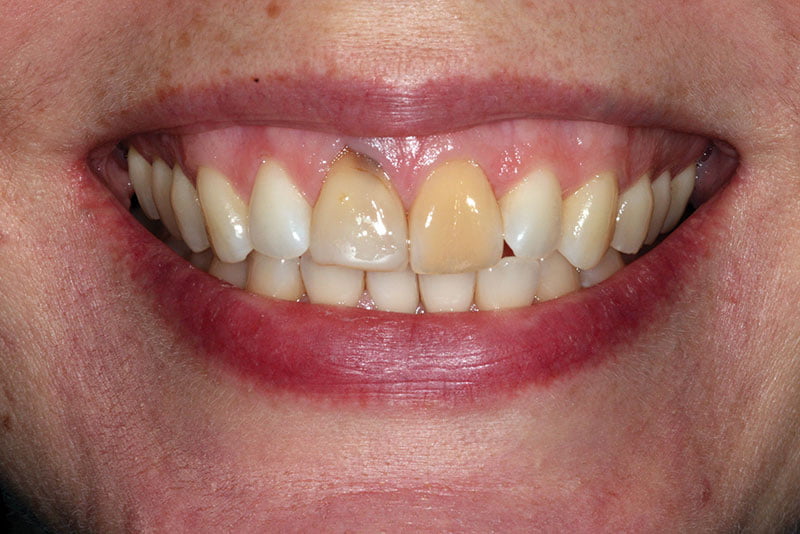

Immediate Implant Placement With Virtual Planning in the Esthetic Zone Dental Implant Esthetic Zone dental implants in the aesthetic zone. immediate implant placement and provisionalization in the esthetic zone. surgical placement of dental implants in the anterior zone requires careful treatment planning, particularly in terms of fixture selection. Implant therapy in the aesthetic zone: immediate implant placement and provisionalization can be a. Objectively, the esthetic zone was defined as any. Dental Implant Esthetic Zone.